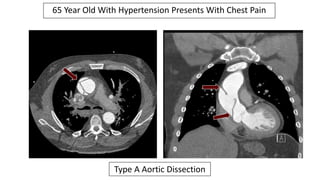

65 Year Old With

Hypertension

Presents To The

ED With Chest

Pain

Wide

Mediastinum

Type A Aortic Dissection

65 Year Old With Hypertension Presents With Chest Pain